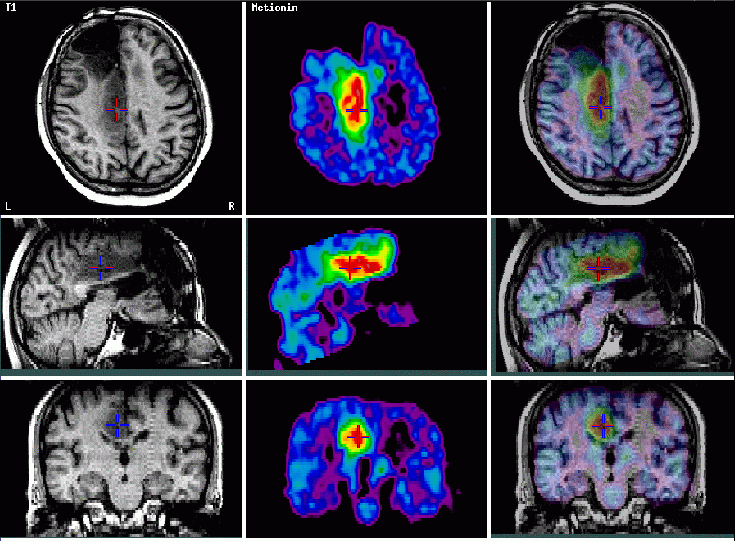

Képfúzió:

Funkcionális és azonos helyzetű strukturális kép együttes

bemutatása

C-11 Metionin PET

Az előző képeken az FDG-t nem dúsító laesio intenzíven halmozza a metionint, ami alacsony malignitási

fokú tumor-recidiva (és nem hegszövet ) mellett szól: